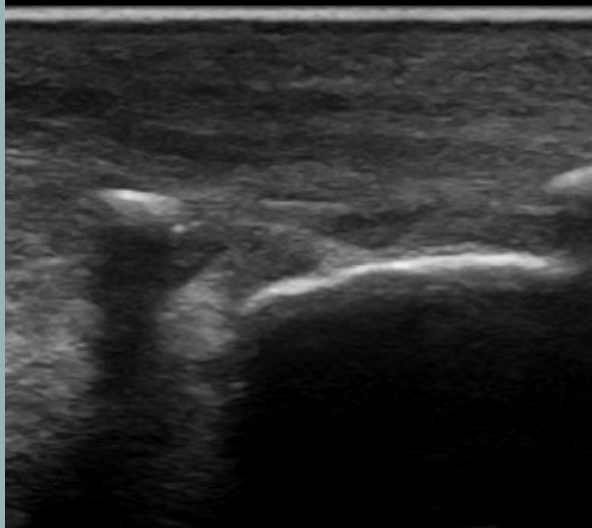

Sombra acústica

- Las ondas de sonido no pueden atravesar una estructura densa (material mineral) o un estrato de gas.

- La imagen generada presenta una línea superficial hiperecogénica que describe la superficie de la estructura, a partir de la cual, pierdo completamente la visualización de los estratos profundos (región oscura).

- Sombra acústica: zona negra detrás de estructuras muy densas como hueso o cálculos.